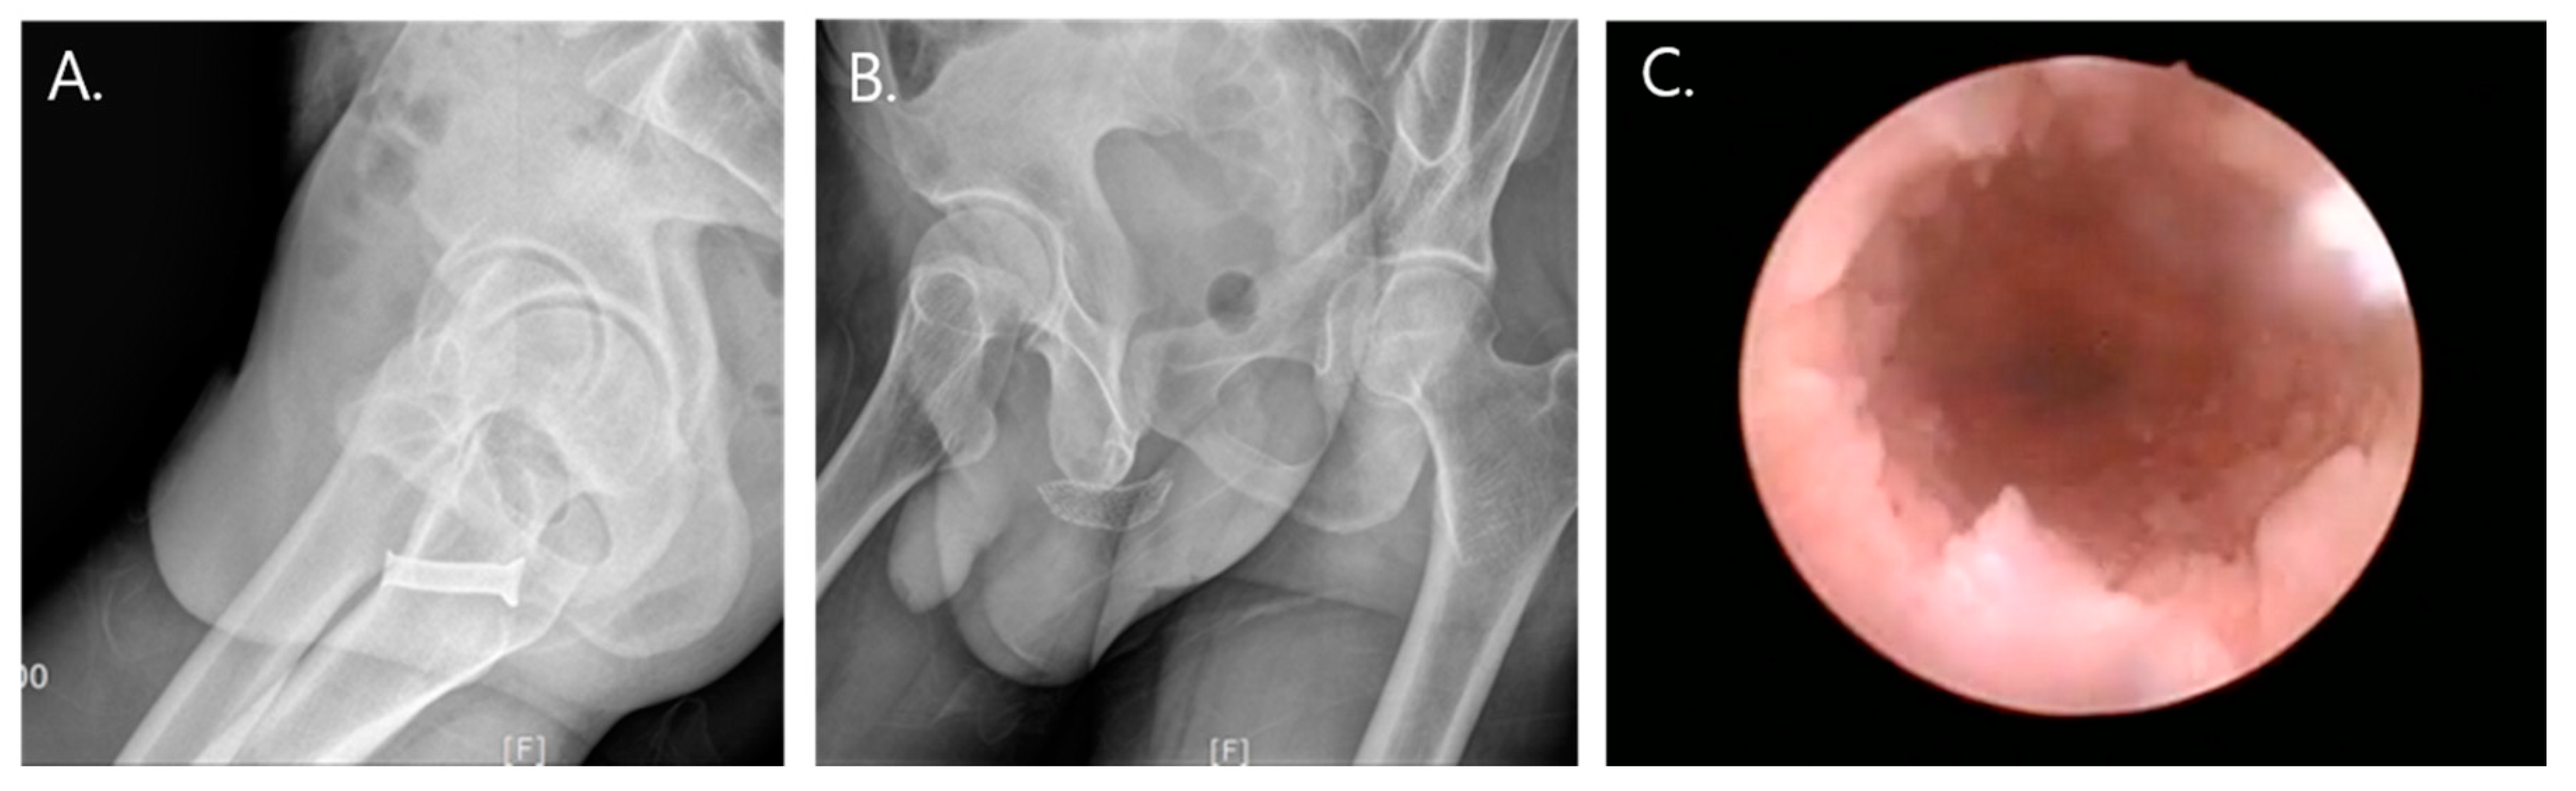

All stents were planned to be removed within 6 months. The patients were placed in the lithotomy position, and the stent removal procedures were performed under local or general anesthesia according to the patients’ preferences. After stent removal, we explored the previous rupture site under urethroscope. There were no wound contractions and circumferential scar formations that resulted in stricture at the previous rupture site (Figure 2).

Figure 2. (A,B) Temporary urethral stents indwelled over the previous rupture site (A: Memokath, B: Allium bulbar urethral stent). (C) Urethroscopy after stent removal.